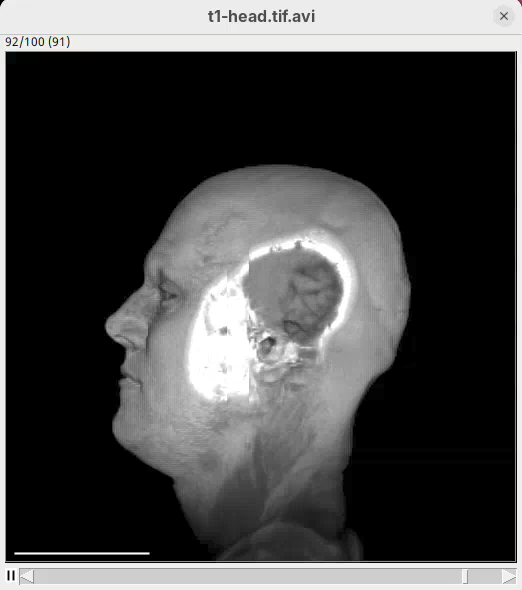

- After the first sentence, write the two commands as shown below:

From frame 0 to frame 35 rotate by 360 degrees horizontally

From frame 36 to frame 71 change channel 1 bounding box min z to 60

From frame 72 to frame 99 change channel 1 bounding box min z to 0- Press

Run.

The script is saying to rotate 360 degrees horizontally, as before, set the Z range minimum to 60 (roughly halfway through the sample) for about 30 frames, and then set the Z range minimum back to 0 in the subsequent 30 frames. And that’s what we get.